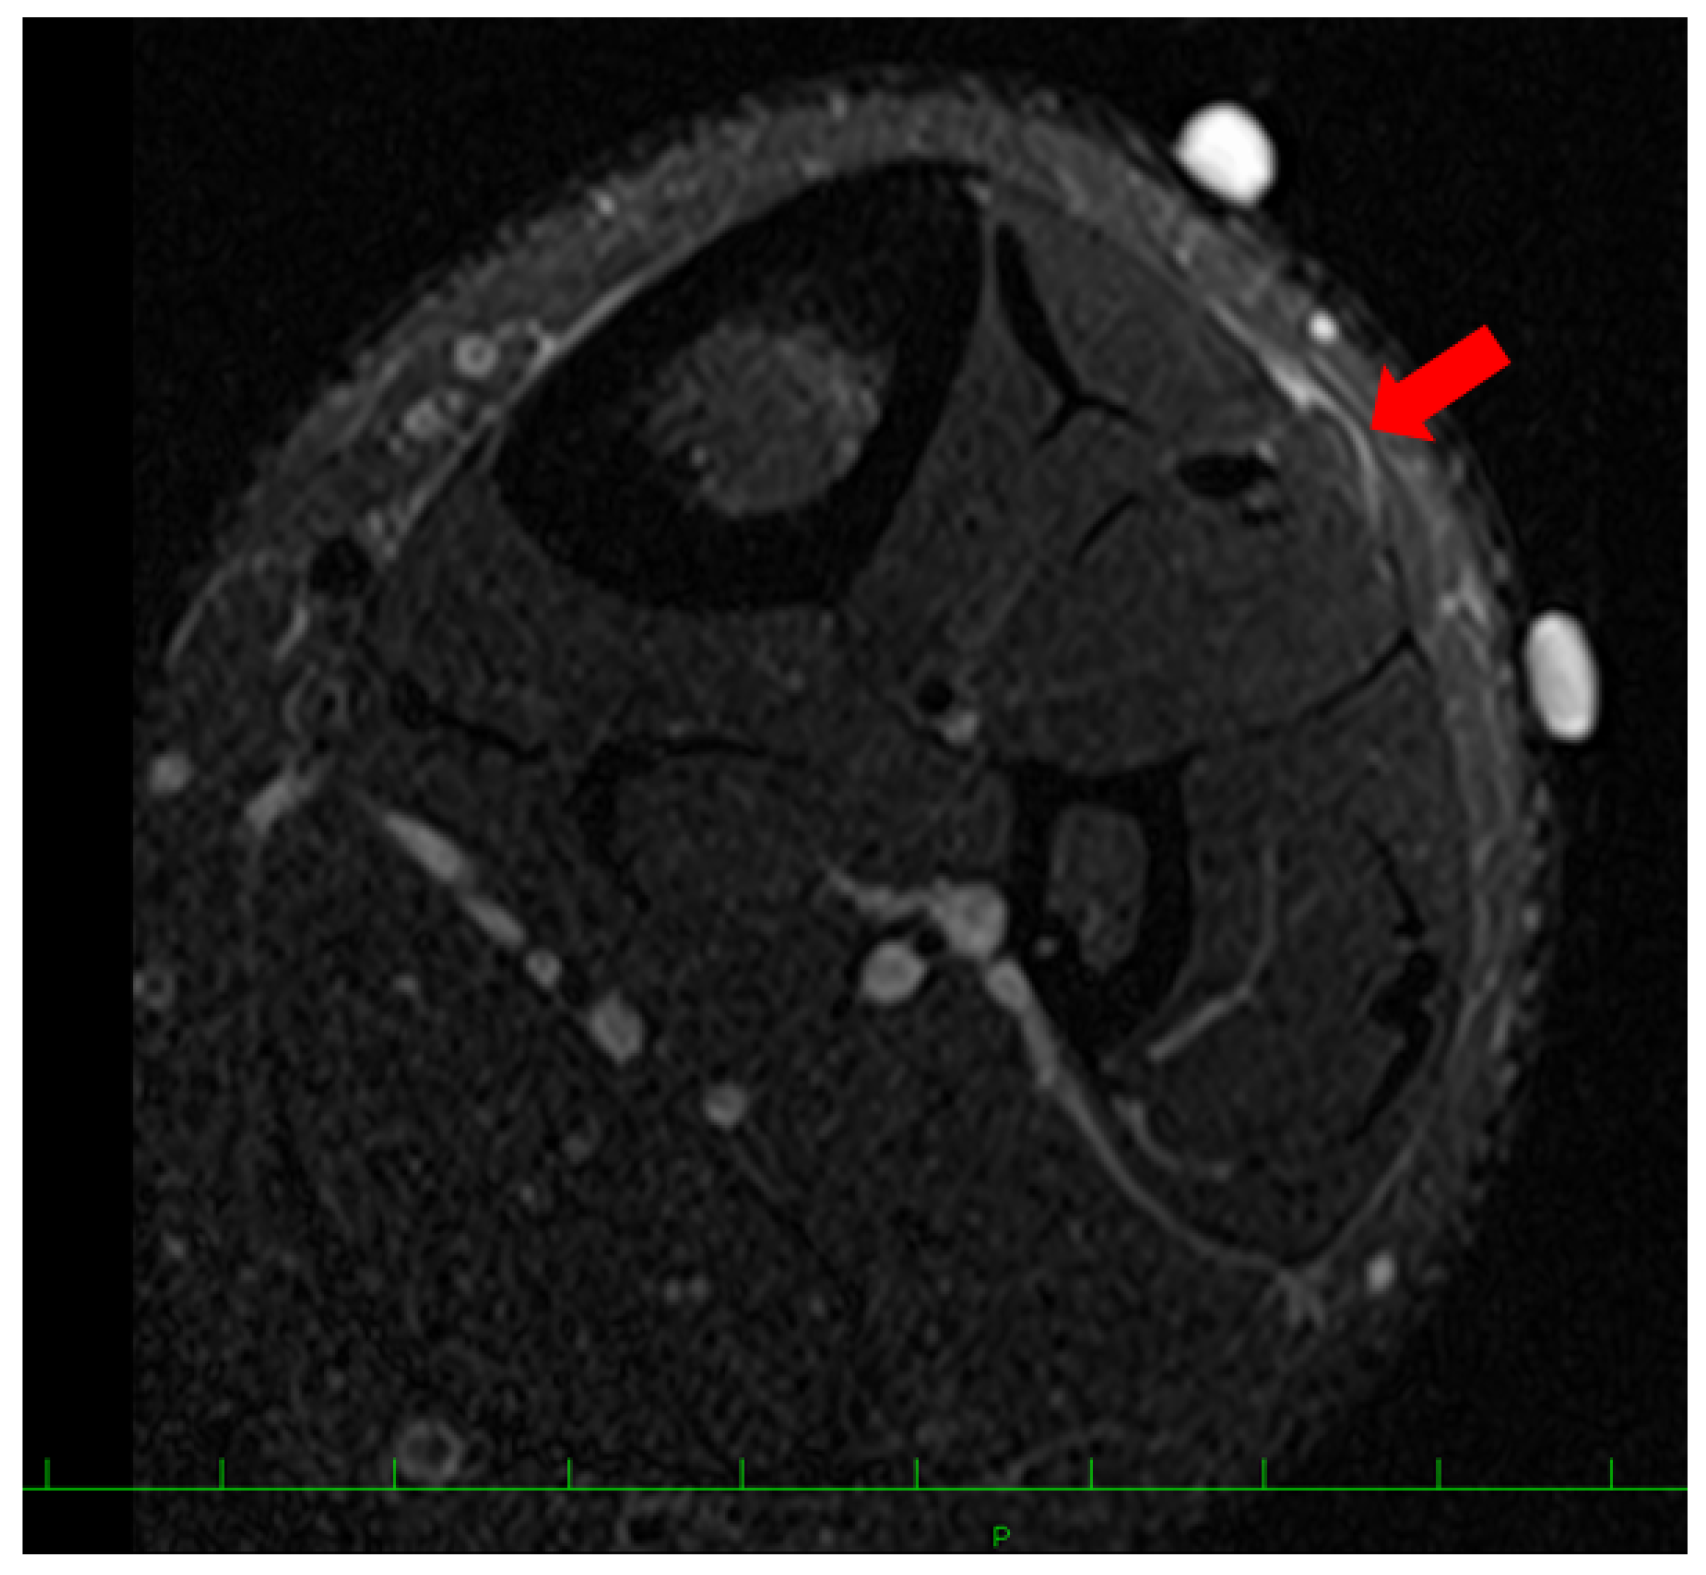

A 16-year-old baseball player was referred to our hospital for the assessment of multiple swelling lesions in the bilateral anterolateral lower legs. He had suffered from painful lesions when playing baseball for about a year, limiting his athletic performance. He had no history of traumatic injuries to the lower legs. Clinical examinations showed bilateral painful swelling lesions (1 on the right and 3 on the left) after dashing (Figure 1). These lesions were concave on palpation at rest. Ultrasonographically, these lesions did not swell with the patient in the supine position but were prominent in the standing position following dashing (Figure 2). Magnetic resonance imaging (MRI) showed a thin or void crural fascia (Figure 3). The preoperative visual analog scale (VAS) was 6/10 when the lesions were symptomatic. The patient was diagnosed with bilateral TAMHs.

Figure 3. Preoperative magnetic resonance imaging (MRI) findings. A slightly swollen lesion (red arrow) of the tibialis anterior muscle with thin crural fascia was detected.